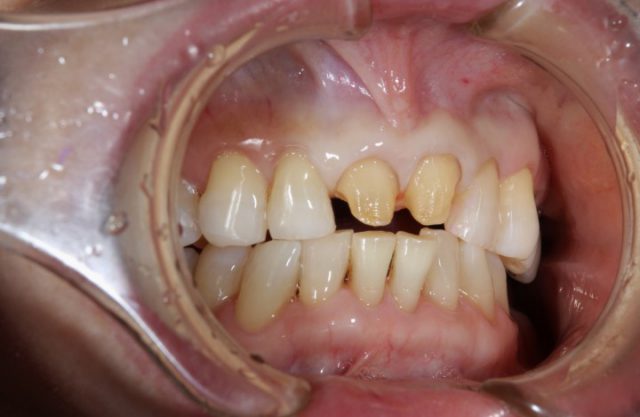

施術中

前歯の被せ物の取り替える場合はまわりの歯との色味をどこまで自然に合わせてくるかが重要になります。せっかく被せ物をやり直すからできるだけ白いものと思ってしまいそうですが、まわりの歯と色味が合わないと白くても違和感が出てきてしまいます。